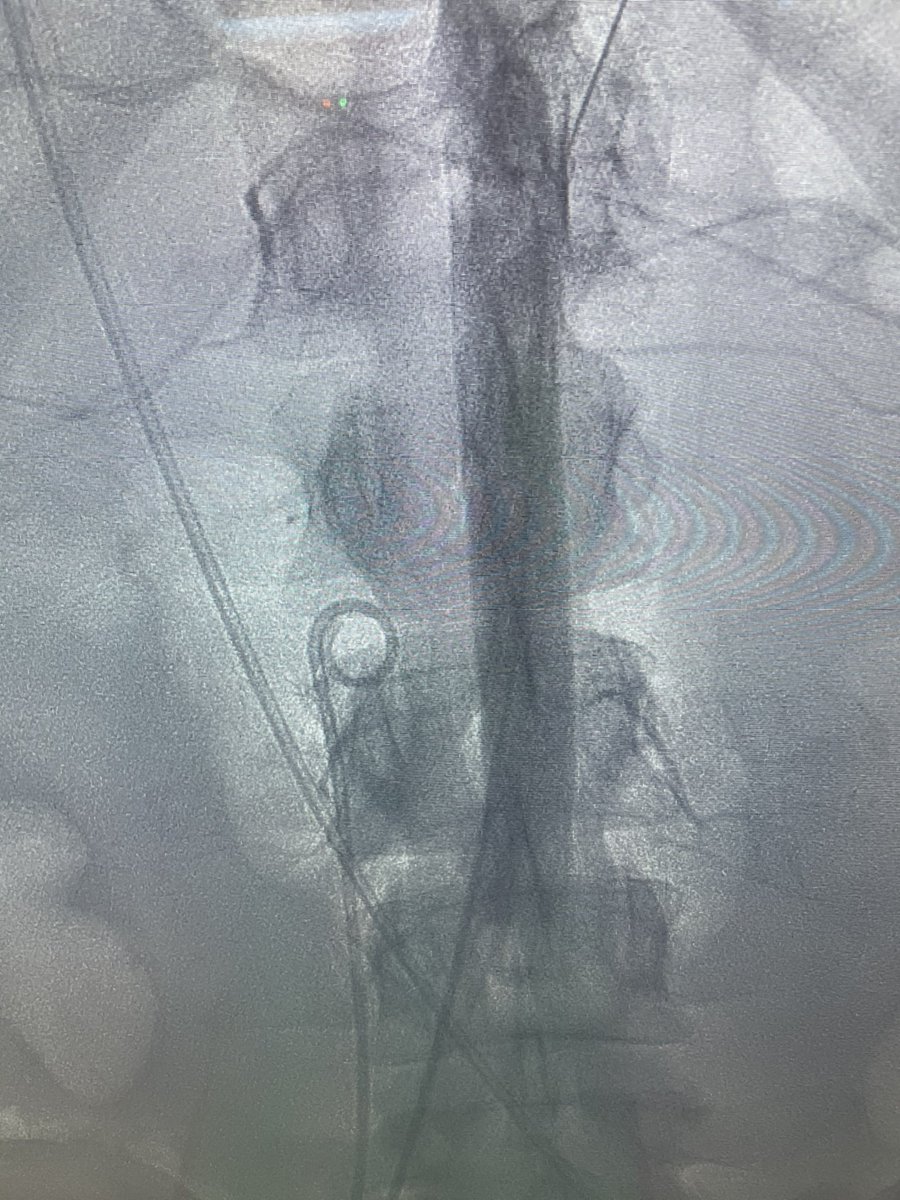

COVID myocarditis in a young obese patient with no other co morbid conditions. Rx with Transcaval 5.0 Impella and Protek. Escalated to ECPELLA. Stable but gaurded. Huge props to @AdamGreenbaumMD virtual support and @NavinKapur4 for curbside consults. Get vaccinated folks.

Dr Chirdeep Patel our MCS fellow did this case skin to skin. Surgical turndown Critical LM with CTO RCA. IVUS guided DK Crush with Impella in CKD patient. Total contrast 48cc. He used CO2 angio for large bore access and completion angio. Awesome to see such expertise.